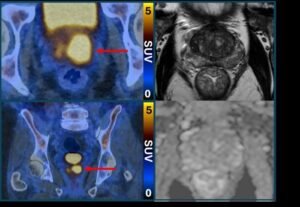

Die PSMA-PET/CT-Untersuchung identifiziert aggressivere Prostatakrebszellen, die potenziell gefährlich sind und behandelt werden müssen. Sie nutzt dazu ein Molekül, das an die Prostatakrebszellen bindet und diese zum Leuchten bringt, sodass sie im Bild als helle Flecken erscheinen. Laut der Studie könnte dies auch dazu beitragen, das Risiko einer Überdiagnose zu verringern, indem festgestellt wird, welche Tumore ein geringes Risiko darstellen und niemals Schaden anrichten werden.

Klinisch signifikanter Prostatakrebs (links, PSMA-PET/CT) trotz normalem MRT (rechts)